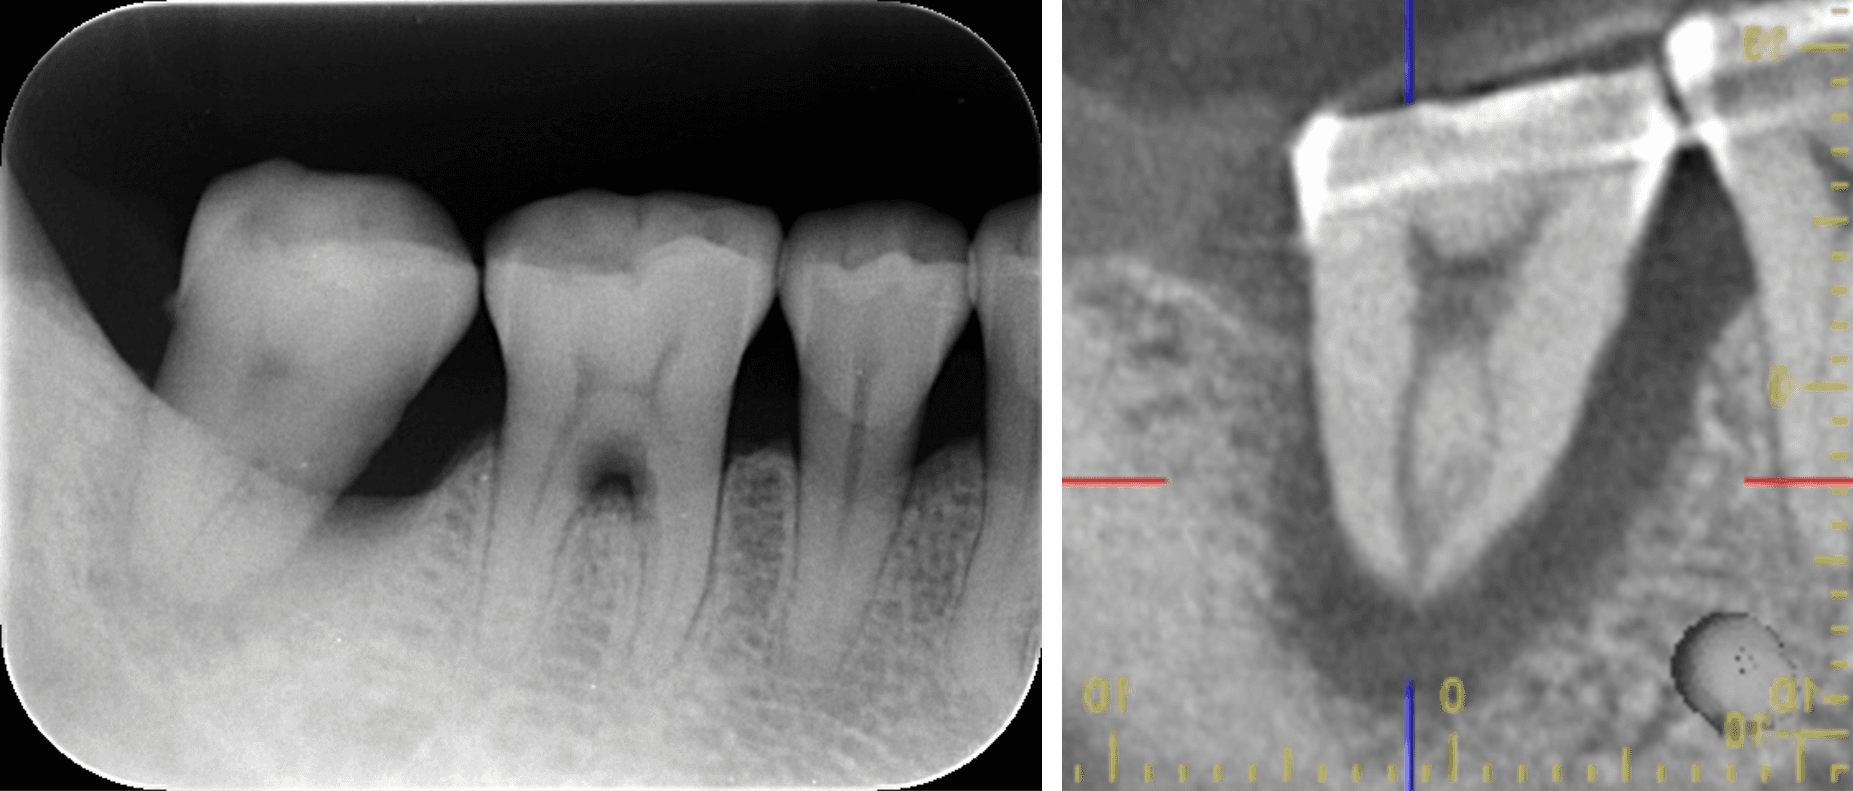

根尖を超える透過像を認める。歯を支えている骨はほとんど残っていない。

レントゲンを撮ったところ、右下の一番奥の歯に根尖を超える透過像がありました。根の下まで支える骨がなくなっているということです。ここまでの状態だとかなり厳しい状況ですが、歯の温存を強く希望されたため、チャレンジな治療になることをご説明し、納得された上で治療を進めることになりました。

根尖を超える透過像を認める。歯を支えている骨ほとんど残っていない。

歯周基本治療後3ヶ月:CTでの評価

透過像が改善されていることが確認できました。細菌が排除されたことで Re-Mineralization(再石灰化)が起きていることも確認できます。

CTでの評価

大幅な透過像の改善が認められました。一見 Hopeless な歯でもエンドも含めた歯周基本治療を徹底し、段階的に診断することで、保存することが出来たと考えます。まだバイオマテリアルの粒子が目立ちますので、今後も経過観察をしていく予定です。